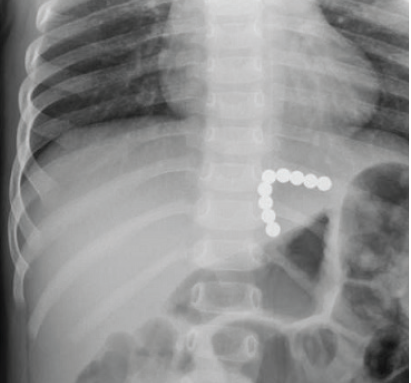

magnet ingestion

01/09/2016

Vrinda Bhardwaj, MD; Quin Liu, MD

A 23-month-old girl was transferred from a local emergency department (ED) to a metropolitan children’s hospital with concern for foreign body ingestion.